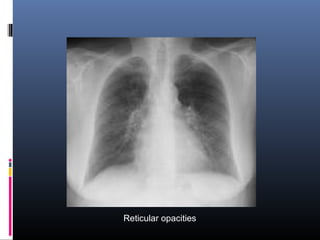

 Reticular, reticulonodular, or focal alveolar

opacities are most characteristic

Reticular opacities

• #23 Reticular opacities